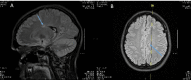

Figure 1. A (Sagittal) and B (Transverse) MRI demonstrating numerous small, non-enhancing periventricular and juxtacortical T2 hyperintensities (arrow).